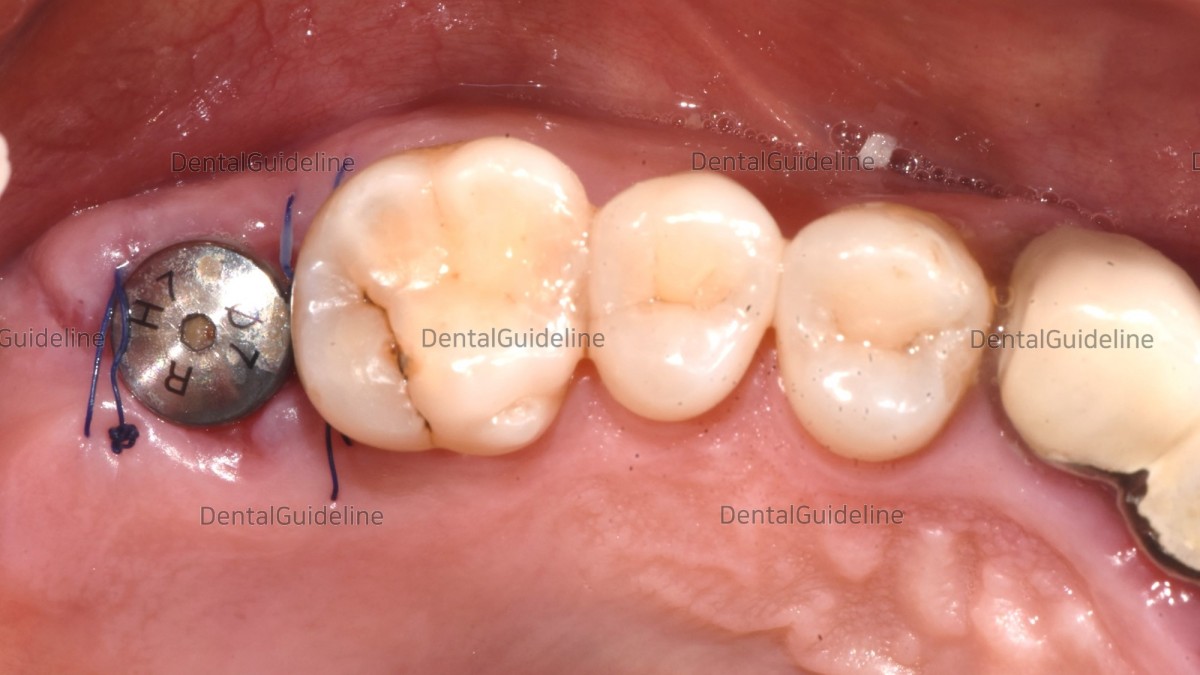

-Collagen membrane and HA.

- Suture.

-Post-op CBCT.

- 2 weeks post-op. photo before suture removal.